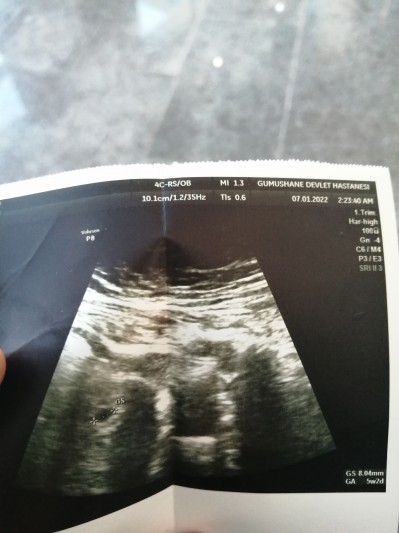

Doktor çok konuşmuyor maşallah ağzı var dili yok.. İlk gebeliğim keseyi anladım ama diğer yazılar ne  yorumlarmısınız

Gebelik haftası 5

5 haftalık kesen var daha bebek ölçümünü yapmamış bı kaç güne ultrasonda görülecek kadar büyücek insallah

Maşallah canım  5+2 günlük gebesin .kese büyüklüğünde 8.04 mm. İki hafta sonra gittiğinde yolsac kesesini  görürsünüz. Kalp atışı da ancak duyulur hale gelir.hayirli olsun canım